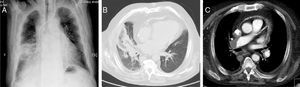

Comunicamos el caso de un varón no fumador de 63 años de edad, que acudió al servicio de urgencias con disnea y fiebre de inicio brusco. La radiología de tórax mostró una opacidad nodular irregular en la región perihiliar derecha (fig. 1A), por lo que el paciente fue hospitalizado en área médica con diagnóstico de neumonía. El estado clínico del paciente empeoró a pesar de la cobertura antibiótica de amplio espectro, por lo que se practicó una TAC torácica que reveló un signo del halo invertido (SHI) en el pulmón derecho (fig. 1B). Este hallazgo dio lugar a un estudio exhaustivo, que incluyó una angiografía pulmonar mediante TAC en la que se demostró la presencia de un trombo en la arteria pulmonar principal derecha (fig. 1C).

El SHI o signo del atolón se caracteriza por la observación de una opacidad en vidrio esmerilado central, rodeada por una consolidación más densa en forma de media luna o circular en el espacio aéreo1.

Aunque inicialmente se consideró un signo patognomónico de neumonía organizada, esta manifestación se ha relacionado con una amplia variedad de enfermedades infecciosas y no infecciosas, entre las cuales se encuentra el embolismo pulmonar (EP)1. En este último caso, el SHI parece que se corresponde con un infarto pulmonar en el EP2 y el diagnóstico se debería fundamentar en los hallazgos clínicos y radiológicos.